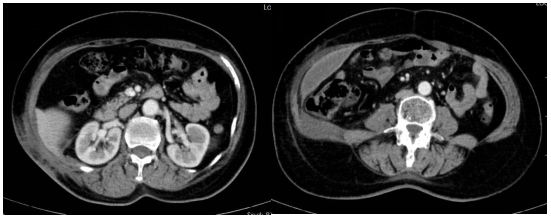

患者先后完成2次空间分割放疗及14次大分割放疗后,腹腔和腹壁肿块逐渐缩小,腰部疼痛完全缓解。放疗结束后3月复查CT显示,原腹腔巨大肿瘤明显消退,仅残留少量低密度软组织影,对肝、肾及小肠的压迫完全解除,腹腔结构及脏器形态基本恢复正常。

经过分割放疗,患者腹腔腹壁肿块逐渐缩小,腰部疼痛完全缓解。